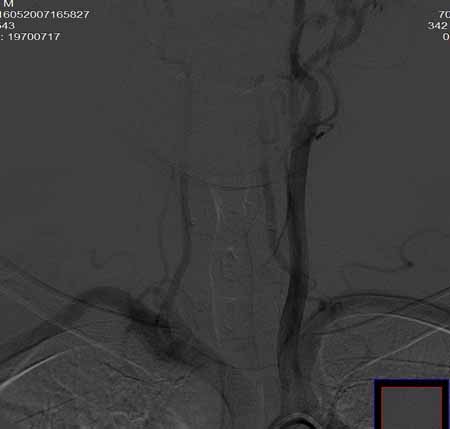

右侧颈总动脉闭塞(血栓形成),左侧大脑前动脉侧支、前交通动脉供应右侧大脑半球

右侧颈总动脉闭塞 ,左侧大脑前动脉侧支、前交通动脉供应右侧大脑半球,后交通部分开放 。缓慢代偿血流,分级3

右侧颈总动脉内见充盈缺损,提示血栓/栓子,原因:

1注意有无心房粘液瘤/血栓

2大动脉炎

抗凝治疗

右侧颈总a闭塞,右颈内颈外未显影,左侧未见异常,并通过wills环代偿右侧大脑半球血供